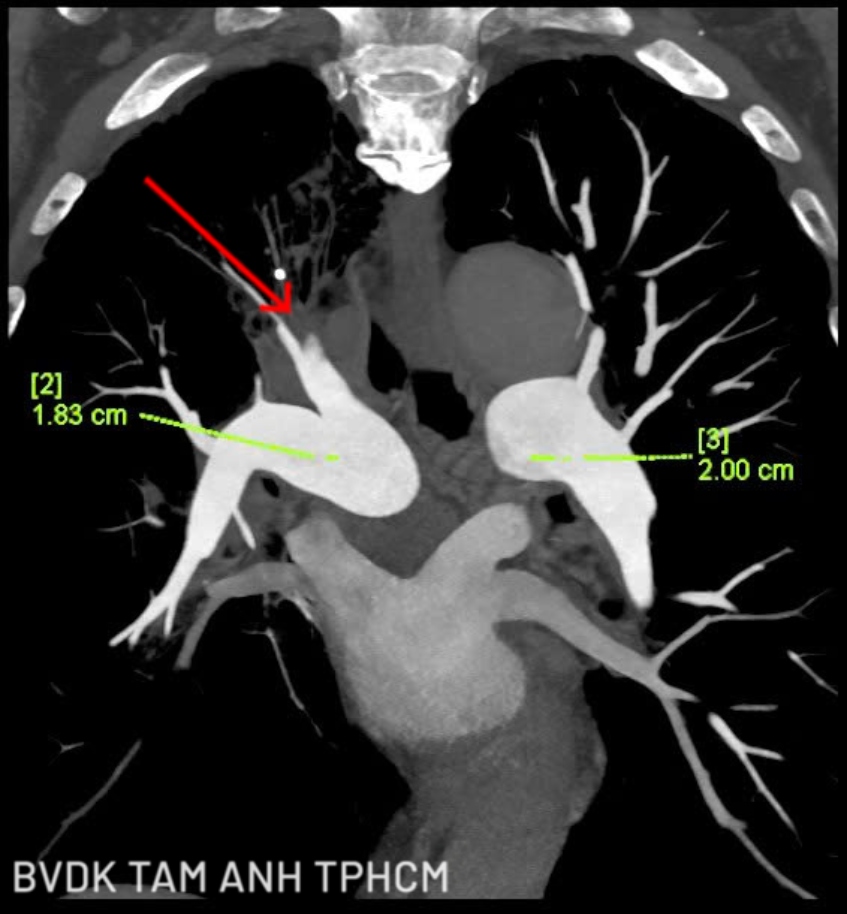

Tuy nhiên ông Kiên tái khám muộn 6 ngày. Tại lần tái khám, ông vẫn còn ho, khó thở giảm nhưng hay mệt. Xét nghiệm D-Dimer cho thấy chỉ số tiếp tục tăng so với 6 ngày trước. Trước diễn tiến này, bác sĩ chỉ định chụp cắt lớp vi tính (CT) Triple Rule Out có tiêm thuốc cản quang, lát cắt siêu mỏng, tái tạo đa thì.

Đây là kỹ thuật chẩn đoán hiện đại giúp đánh giá đồng thời ba nguyên nhân nguy hiểm thường có biểu hiện tương tự nhau là thuyên tắc phổi, bệnh mạch vành và bóc tách động mạch chủ. Kết quả ghi nhận mảng xơ vữa gây hẹp 50–60% động mạch liên thất trước, xơ vữa dọc thành động mạch chủ; đặc biệt, huyết khối lấp hoàn toàn nhánh A1, A2 và đoạn xa của một phân nhánh A3 động mạch phổi phải. Ông Kiên được chẩn đoán thuyên tắc phổi trên nền COPD đợt cấp bội nhiễm, kèm nhiều bệnh lý tim mạch và chuyển hóa.